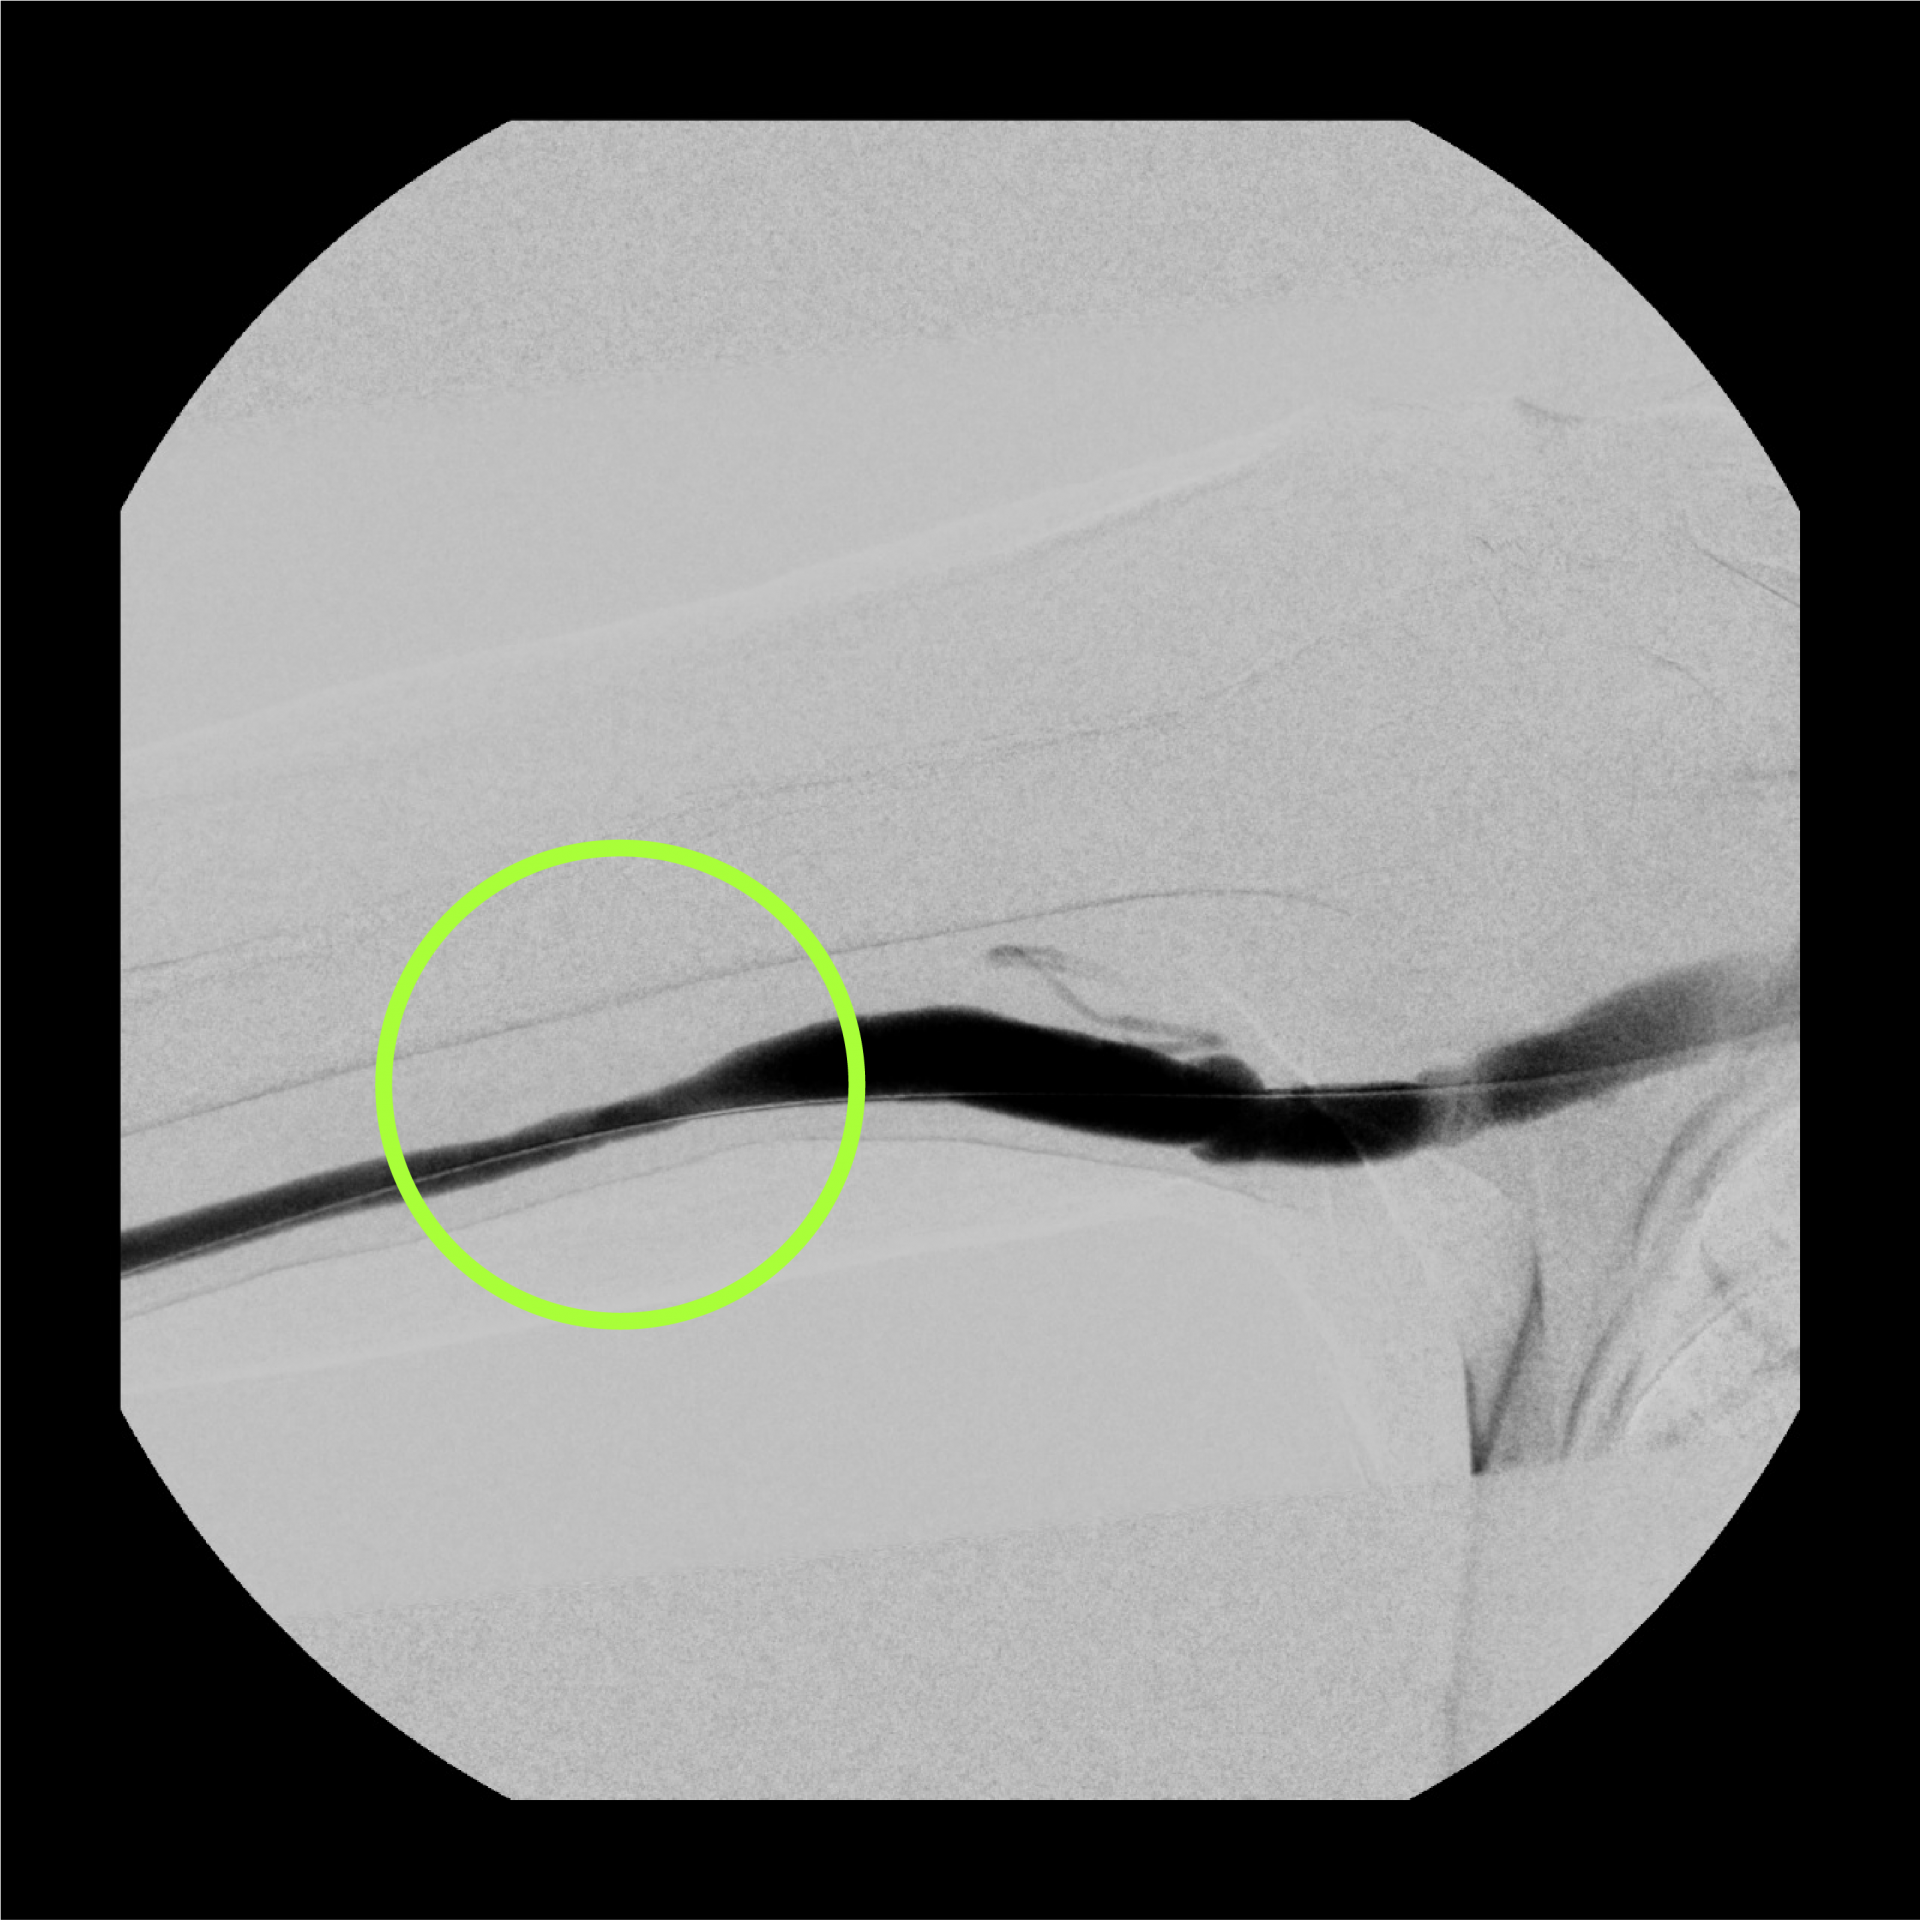

좁아진 투석혈관을 치료하는 대표적인 방법은 풍선확장술(혈관 중재술)입니다. 혈관 조영술로 협착 부위를 확인한 후, 풍선을 이용해 좁아진 부위를 확장합니다.

풍선 시술 전의 모습

1 풍선시술 전

풍선 삽입 과정의 모습

2 풍선 삽입

풍선 시술 후의 모습

3 풍선시술 후